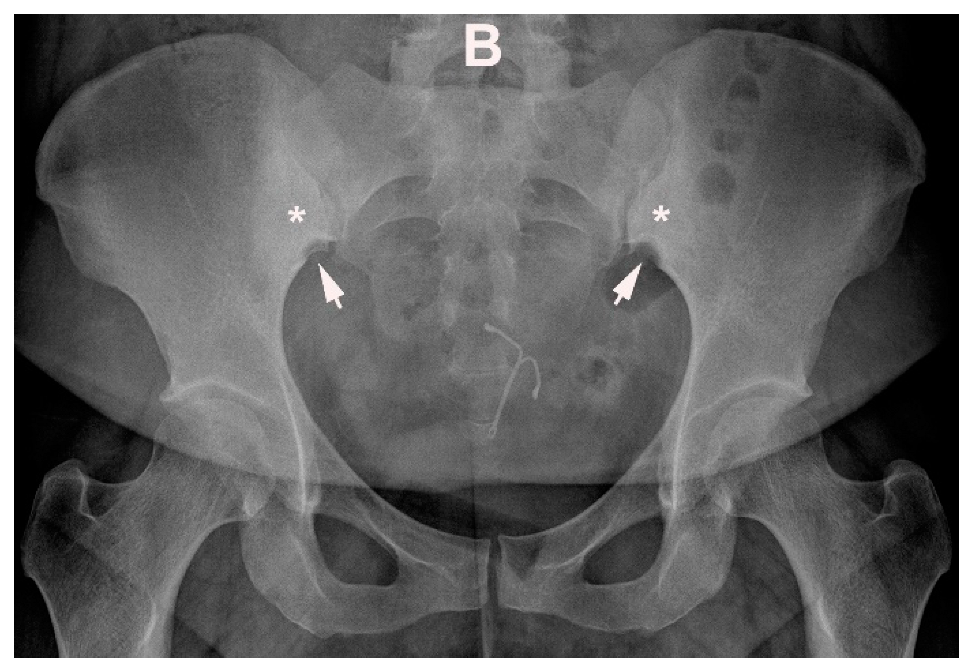

12. Hyperparathyroidism and Other Disorders of Mineral Metabolism

6. Other Strain-Related SIJ Changes